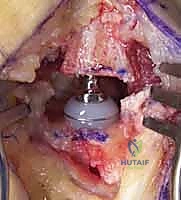

1. استئصال العظم المربعي مع إعادة بناء الأربطة (Trapeziectomy with LRTI)

تُعد هذه العملية "المعيار الذهبي" (Gold Standard) والأكثر شيوعاً ونجاحاً عالمياً لعلاج هذه الحالة.

• آلية العملية: يقوم الجراح بإزالة "العظم المربعي" (Trapezium) بالكامل، وهو العظم الذي يسبب الاحتكاك المؤلم. بمجرد إزالته، يختفي الألم تماماً لأنه لم يعد هناك عظم يحتك بعظم.

• **إعادة بناء الأربطة (LRTI):